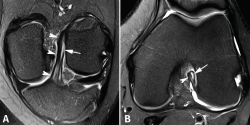

El protocolo de estudio por RM debe incluir secuencias en densidad protónica (DP) con supresión selectiva de la grasa en los 3 planos ortogonales. La valoración del LCA debe realizarse combinando la información de todos los planos. En el plano sagital, con frecuencia resulta complicado diferenciar tanto la anatomía fascicular como la inserción proximal. Los cortes coronales y axiales sucesivos son los más útiles para valorar con precisión la anatomía fascicular y las lesiones parciales del LCA (Figura 2).

Figura 2. Anatomía normal del ligamento cruzado anterior (LCA) en secuencias convencionales de resonancia magnética (RM). A: corte sagital potenciado en densidad protónica (DP) con supresión grasa que muestra en toda su extensión el trayecto del fascículo anteromedial (AM); B: corte coronal de RM potenciado en DP con supresión grasa que muestra la anatomía bifascicular. PL: fascículo posterolateral.

Las secuencias FSE 3D isotrópicas con diferentes nombres comerciales (Space®, Cube®, Vista®, MPV®...) permiten realizar reconstrucciones multiplanares, incluyendo planos oblicuos adaptados al trayecto del LCA(10,11,12,13,14). Estudios recientes muestran que estas secuencias tienen una precisión similar a las secuencias 2D convencionales en la valoración de las lesiones intraarticulares de rodilla. Sin embargo, las imágenes reconstruidas con estas secuencias FSE 3D muestran un mayor grado de distorsión geométrica que dificulta valorar específicamente las lesiones parciales del LCA. La realización de cortes milimétricos oblicuos 2D DP con campo de visión reducido en los planos coronal (siguiendo el trayecto del LCA) y axial (perpendiculares al LCA) permiten obtener imágenes de alta resolución espacial que facilitan una valoración más fiable de las lesiones parciales del LCA(15)(Figura 3).

Figura 3. Anatomía normal del ligamento cruzado anterior (LCA) en cortes oblicuos de resonancia magnética (RM). A: corte oblicuo coronal de RM potenciado en densidad protónica (DP) con supresión grasa adaptado al trayecto del LCA que muestra la anatomía bifascicular normal; B: corte oblicuo axial de RM potenciado en DP con supresión grasa perpendicular al trayecto del LCA que permite valorar el estado de ambos fascículos. AM: fascículo anteromedial; PL: fascículo posterolateral.